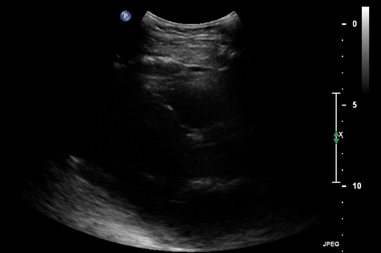

Throughout the case, the patient was managed with total doses of 0.7mg norepinephrine, 9.0mcg epinephrine, 0.4mg phenylephrine, and 23mg dobutamine while using 1L of lactated ringer to maintain adequate blood pressure. Norepinephrine has mixed alpha-1 and beta activity and was used to increase systemic vascular resistance and support myocardial contractility, leading to an increase in blood pressure and cardiac output. Epinephrine has comparable activity on alpha-1 and beta receptors and was used to increase systemic vascular resistance, heart rate, cardiac output, and blood pressure which ultimately provided additional inotropic support. Phenylephrine is an alpha-1 agonist and was given to induce peripheral arterial vasoconstriction, providing improvement in vascular tone and enhancing perfusion pressure.5 During the case, the patient continued to be hypotensive with blood pressures dropping down to 100/40mmHg and dobutamine, a beta-1 agonist with positive inotropic effects, was introduced at 19:38 to enhance cardiac output by increasing myocardial contractility.5 The thrombectomy was completed uneventfully and tolerated well by the patient (Figure 1-3).

Figure 1 Transthoracic echocardiogram (TTE) in the parasternal long-axis view at end-systole. The image demonstrates a dilated left ventricle with reduced contractility and decreased ejection fraction, indicative of acute heart failure. The left atrium appears enlarged, suggesting elevated filling pressures.